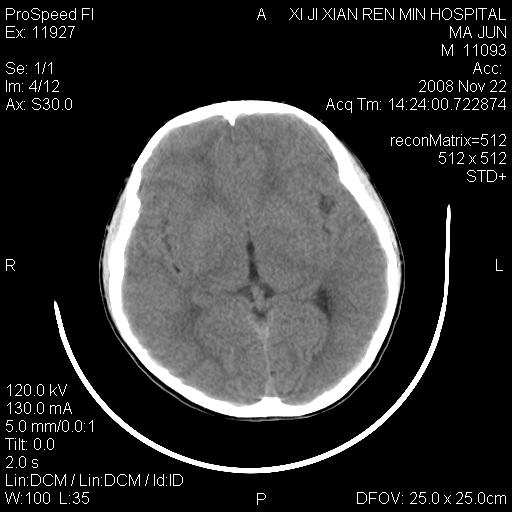

双侧侧脑室前角,三角区旁及半卵圆中心区白质呈低密度改变,半卵圆中心区病灶呈片状融合趋势,无软化征像,脑室无扩张,各神经核团无异常改变,脑皮质无萎缩等征像,结合病史考虑髓鞘发育不良性脑白质病,异染性脑白质营养不良可能性大.不除外多发性硬化等其他改变,建议磁共振检查

脑白质减少,双侧侧脑室额角旁及半卵圆中心可见对称性略低密度影,边缘尚清,考虑脑白质发育不良